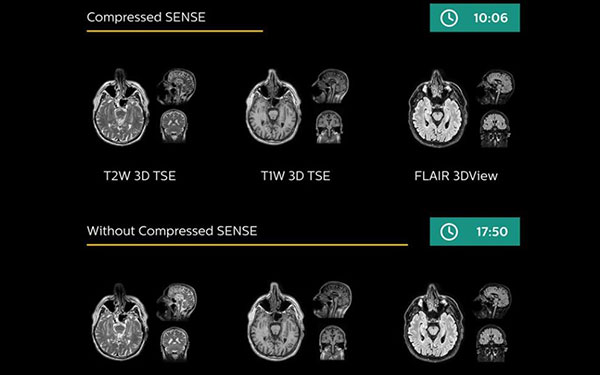

Accelerate exams by up to 50%1

Fast overall exam-time is achieved through Compressed SENSE applied in dedicated RT ExamCards. This enhanced version of innovative SENSE technology accelerates both 2D and 3D scans by up to 50% with virtually equal image quality. This shortens the time the patient is in the scanner and can help to manage intra-scan motion.